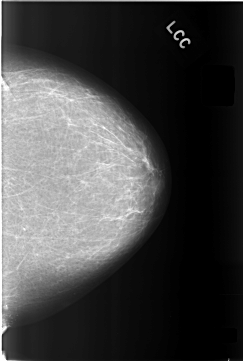

C_0305_1.LEFT_CC

LEFT_CC LINES 5776 PIXELS_PER_LINE 3888 BITS_PER_PIXEL 12 RESOLUTION 50 NON_OVERLAY

LEFT_MLO LINES 5720 PIXELS_PER_LINE 3904 BITS_PER_PIXEL 12 RESOLUTION 50 NON_OVERLAY